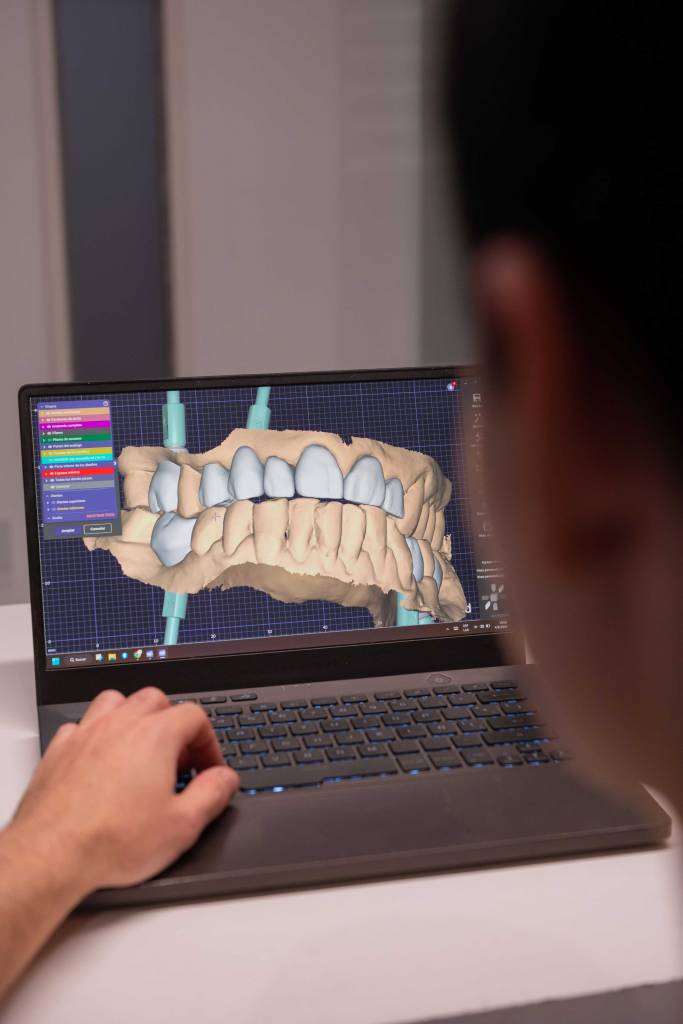

En nuestro consultorio, los implantes son colocados en la boca del paciente a través de guías quirúrgicas de precisión, diseñadas digitalmente por nuestro propio odontólogo cirujano a partir de la tomografía 3D del paciente y su escaneado intraoral. Estas guías son fabricadas en nuestro laboratorio dental digital, lo que nos permite planificar la cirugía con altísima precisión, optimizar el posicionamiento del implante y reducir el margen de error.

Gracias a esta tecnología, las cirugías son más rápidas, menos invasivas y con un mejor postoperatorio reduciendo significativamente los tiempos de recuperación, brindando al paciente una experiencia segura y de excelencia.

Realizamos todo el proceso de manera personalizada, desde la planificación digital hasta la colocación definitiva, sin depender de terceros, garantizando precisión y calidad en cada caso.